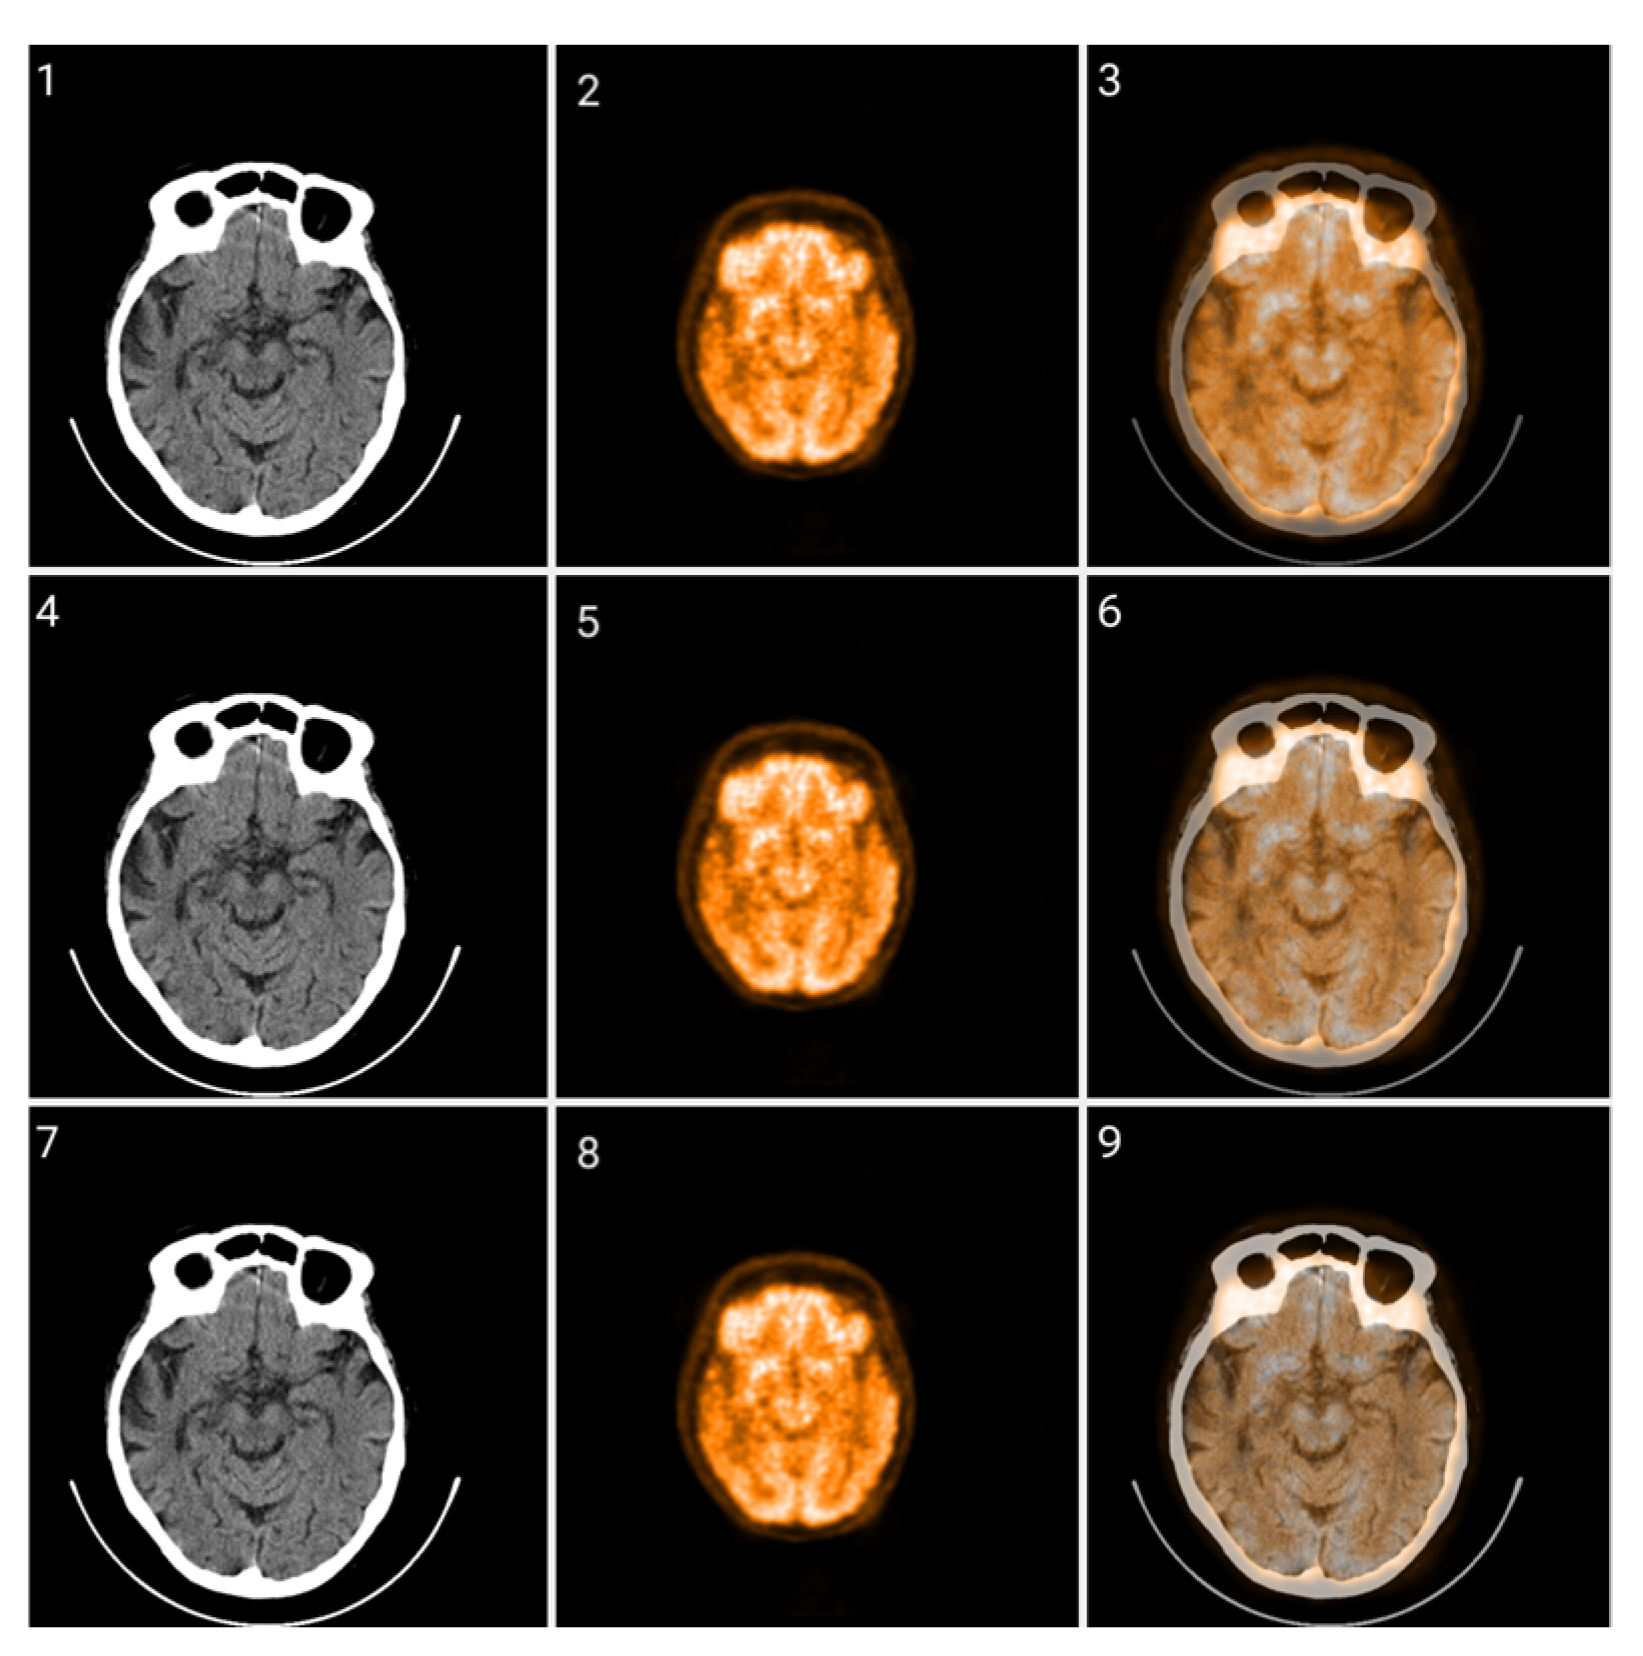

2.2. Method 1: Colormap Information Transform (CIT)

3.1. CIT Application

3.2. Colormap Folding Application